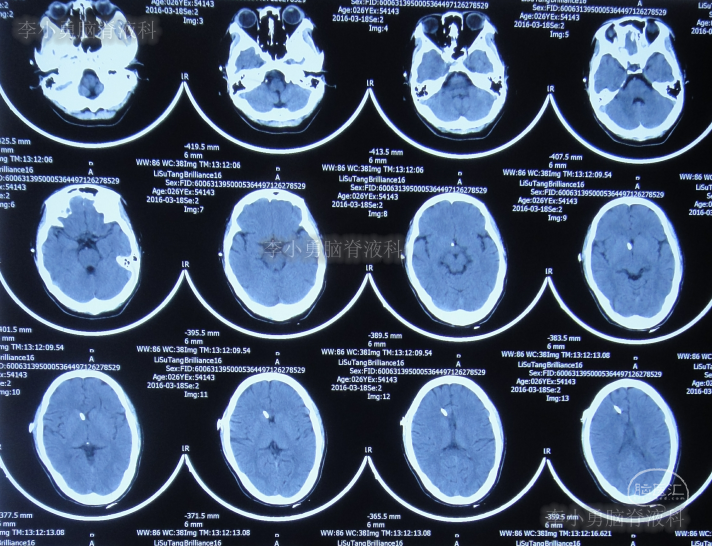

第三家医院第3次门诊图-1

图-1:2016年3月18日头颅CT